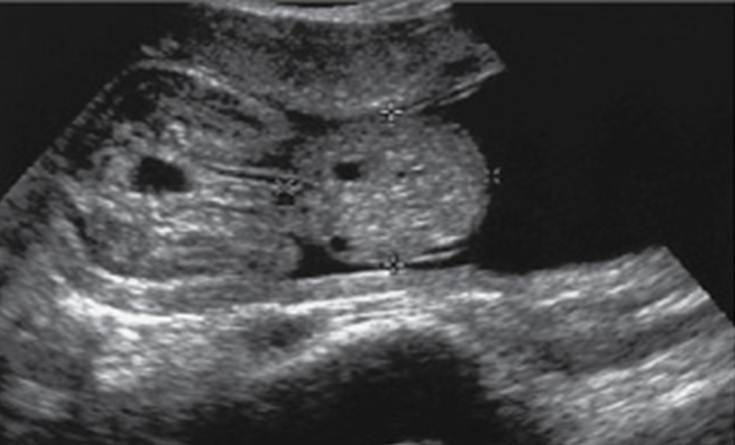

“Double bubble” sign as seen with duodenal atresia